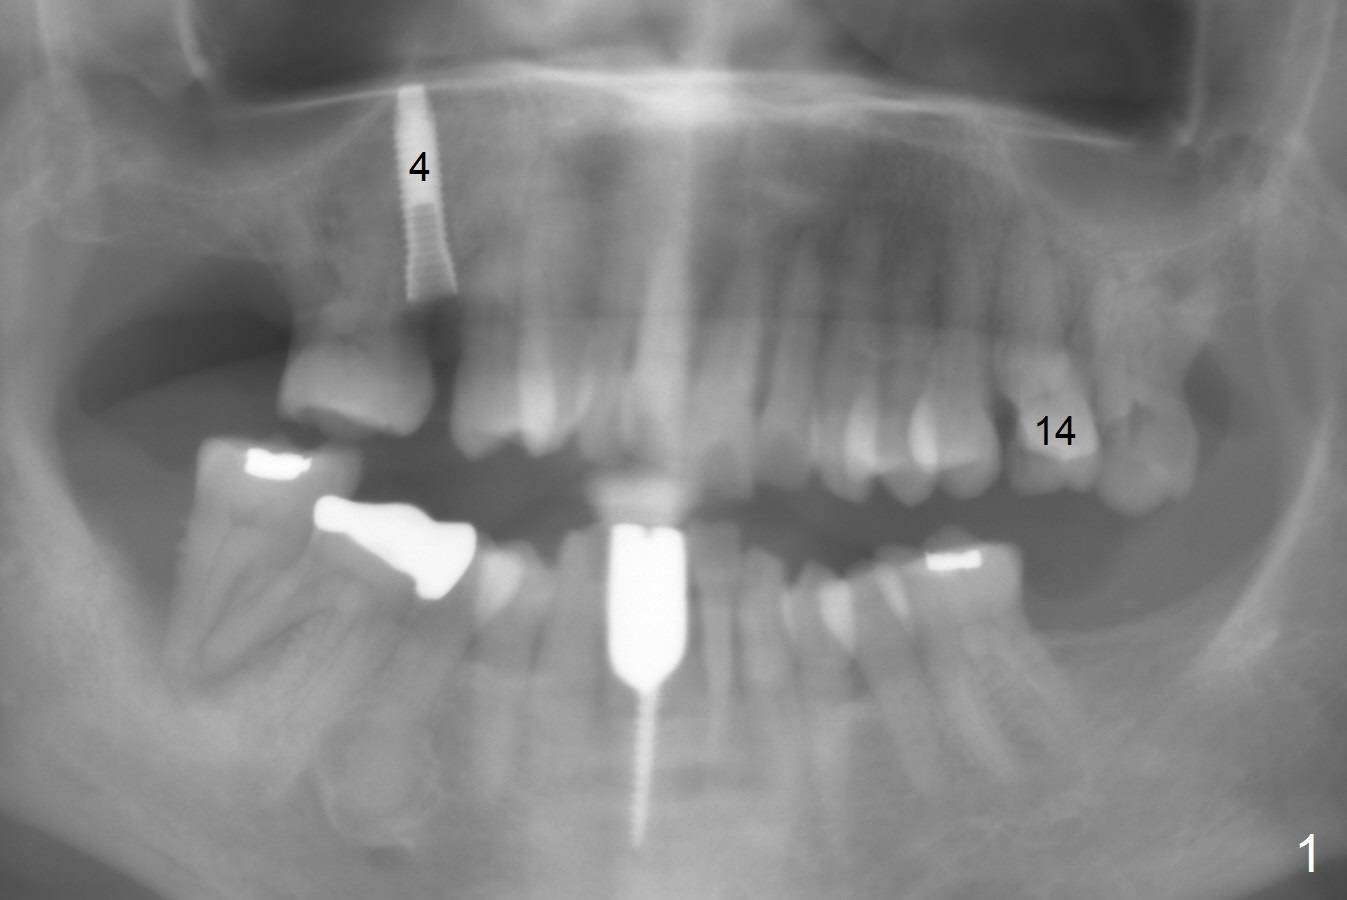

A 65-year-old woman cracks the tooth #14 prior to #4 implant (Fig.1). The height of the septum is ~ 10 mm; initial osteotomy depth will be 8.5 mm; 1-2 mm from the sinus floor. While increasing the drill size, check whether there is perforation on the side of the osteotomy apically. Since the patient is small, start low dose of X-ray.